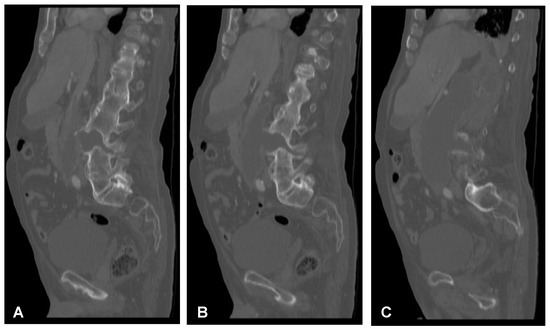

2.4. Surgery of the Cervical Spine Due to the Tetraparesis

Following the initial diagnostics, the patient was transferred to the operating room. The combined anterior and posterior osteosynthesis (360° fixation) at the C4-C5-C6-C7 levels were performed. In the first stage of surgery, the anterior stabilization plate (50 mm) and locking screws (Zephir; Medtronic, Minneapolis, MN, USA) under intraoperative 2-D fluoroscopy control were placed. In the second stage of surgery, the patient was turned and posterior-stabilized (Ellipse; Globus Medical, Audubon, PA, USA) with lateral mass screws (8 mm × 14 mm) using free-hand technique based on anatomical landmarks due to poor intraoperative visualization of cervicothoracic region capabilities using 2-D fluoroscopy was performed. A control CT scan performed one day after the operation revealed the correct placement of all the implants (Figure 9). After surgery, the patient remained in deep tetraparesis with minimal movements in the lower limbs but no movement in the upper limbs. Early postoperative rehabilitation at the bedside was initiated. However, the patient remained prolonged endotracheally intubated but was conscious and awake due to the retention of airway secretions, as well as was parenterally fed for 5 days. The patient was empirically administered intravenously with amoxicillin with clavulanic acid (1 g/0.2 g every 12 h). After successful extubation, the tracheostomy and percutaneous endoscopic gastrostomy (PEG) were not performed. After 12 days, the patient was discharged with no signs of infection and transferred to the rehabilitation center.

Figure 9. Postoperative sagittal CT scans (non-contrast enhanced) after the two-stage surgery of the cervical spine demonstrating placement of the anterior plate with locking screws (A) and posterior lateral mass screws (B) at the C4-C5-C6-C7 levels.